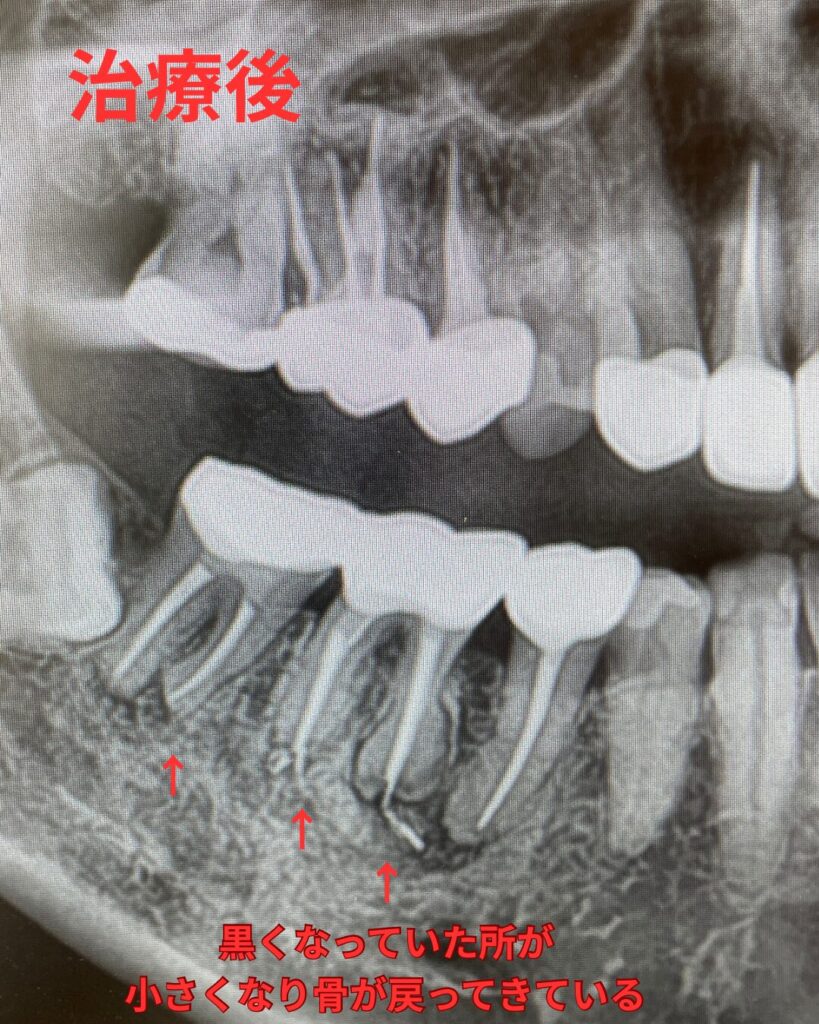

レントゲンの治療前後の比較

精密根管治療前後のレントゲン写真です。

初回治療後より痛みがなくなり、とても快適に過ごせているとお言葉をいただきました。根管治療が奏功し炎症が引いているのが確認できたたため、最終的な治療を行い型取りを行いました。最終の修復はジルコニアクラウンです。